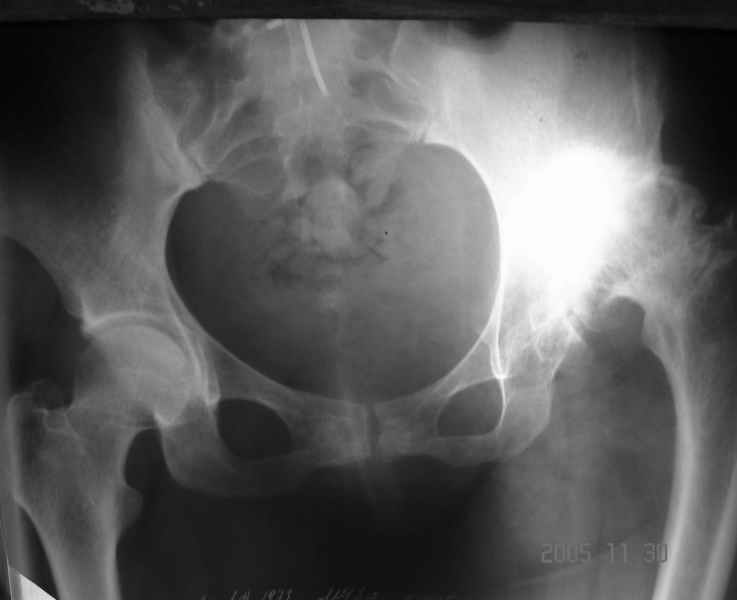

Уважаемые коллеги, прошу дать совет по данному случаю. Пациентка 32 лет с диспластическим левосторонним коксартрозом 3 ст. Из анамнеза - в детстве операции по поводу врожденного вывиха левого бедра (остеотомия таза по Хиари и остеотомия проксимального отдела бедра, аппаратное удлинение голени) В настоящее время беспокоят боли в левом тазобедренном суставе, ограничения движения (сгибание 60 гр, отведение 20 гр, общ ротация 30 гр); укорочение левой н/конечности на 5 см. Пациентка ставит задачу о полноценности тазобедренного сустава и коррекции длины нижней конечности. Р-гр прилагаются. Какой тип эндопротеза оптимален в данном случае? Как проводить коррекцию укорочения? (аппаратное удлинение голени после протезирования?)Буду весьма благодарен за помощь.

Если подходить к заданным Вами вопросам академически, то в обязательном порядке необходима Р-грамма в аксиальной проекции, особенно учитывая перенесенную МВО, т.к. возможны деформации, не видимые на представленных снимках. Если ориентироваться только на то, что Вы прислали, то я не вижу больших проблем с выбором бедренного компонента - обычная ножка клиновидной формы из того ряда что Вы имеете в своем выборе.

Другой и самый сложный вопрос - расположение и фиксация вертлужного компонента. На мой взгляд, оптимальное решение - расположение чашки в анатомическом положении с компенсацией недопокрытия за счет аутокостной пластики (из удаленной головки). Если Вы подниметесь выше (более 2,5-3 см), то велика опасность проваливания в полость малого таза, т.к. предсказать истинную анатомию после перенесенной остеотомии таза про Хиари крайне сложно. Как показывает опыт, после такой остеотомии лучше не верить картинке стандартной Р-граммы, а ориентироваться на анатомическое положение фигуры слезы. Хорошим решением была бы КТ.

Уважаемый Алексей! На наш взгляд пациентке необходимо выполнить бесцементное эндопротезирование. Особое внимание уделить формированию имплантационного ложа чашки протеза -симметрично контрлатеральному суставу. То есть центрировать фрезу в истинную acetabulum, а не во впадину неоартроза. Причем использование небольшого размера (44-46 мм) впадины протеза позволит её надежно закрепить в тазовой кости без какой-либо костной пластики. Если будет выраженный пороз тазовой кости, то следует предусмотреть впадину с цементной фиксацией. Укорочение нивелируется после протезирования. Дополнительно ничего удлинять не надо. Но имеется вальгус коленного сустава, который возможно придется устранять корригирующей надмыщелковой остеотомией.

Аксиальная рентгенограмма подтверждает, что Вы имеете дело со стандартным случаем диспластического коксартроза. Смею присоединиться к мнениям коллег